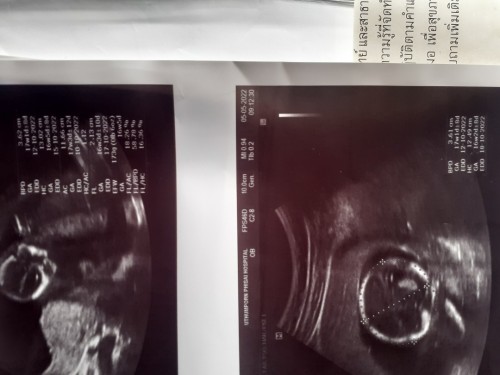

อยากทราบว่าน้องโตตามอายุครรภ์ไหมคะตอนที่ซาวด์ได้16วีค3วันคะ อยากทราบว่านน.ขนาดน้อง ตามเกณฑ์ไหมคะ